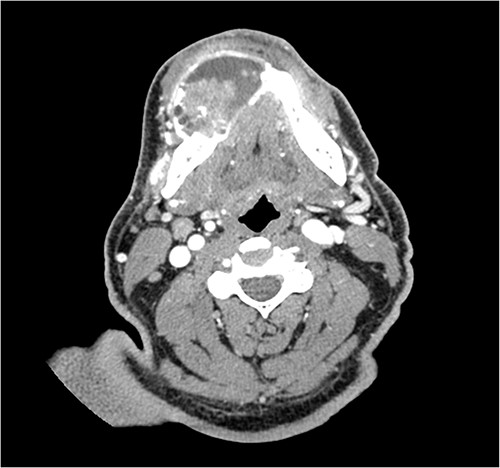

A 52-year-old male presented with a 4-month history of right lower lateral lip swelling and dental complaints. On physical examination, there was a large right mandibular mass with several floating teeth extending from the symphysis to the angle (Fig. 1). The patient’s history was notable for hypertension and a 36-pack year smoking history. He denied any other concerning symptoms. Computed tomography (CT, Fig. 2) imaging demonstrated at large heterogeneous, multiloculated, expansile lesion of the right mandible. An incisional biopsy was performed, and results demonstrated epithelial tumor islands with columnar cells exhibiting peripheral palisading, stellate reticulum-like areas, granular cells, and reverse polarization (Fig. 3). Following diagnostic confirmation of multicystic granular cell ameloblastoma, the patient underwent successful surgical resection and reconstruction. Final pathology showed a 5.0-cm granular type conventional multicystic ameloblastoma with negative surgical margins. At time of report, 7 years after resection, our patients is alive with no evidence of recurrence.

CT imaging demonstrating the heterogeneous, multiloculated, expansile lesion stretching in the buccal-lingual direction.

On CT, multicystic granular cell ameloblastomas present as a multilocular radiolucent destruction of bone, appearing as a honeycomb or soap bubble appearance. Anatomically, they are not confined to the alveolar bone and routinely perforate cortical bone. These findings are not pathognomonic, and thus, other odontogenic diagnoses, such as odontogenic keratocyte and central giant cell granuloma, must be considered as well [3]. Radiologically, granular cell ameloblastomas typically expand in the buccal-lingual direction, which can be seen in our patient (Fig. 2). While helpful, radiology is only supplemental in determining a final diagnosis.